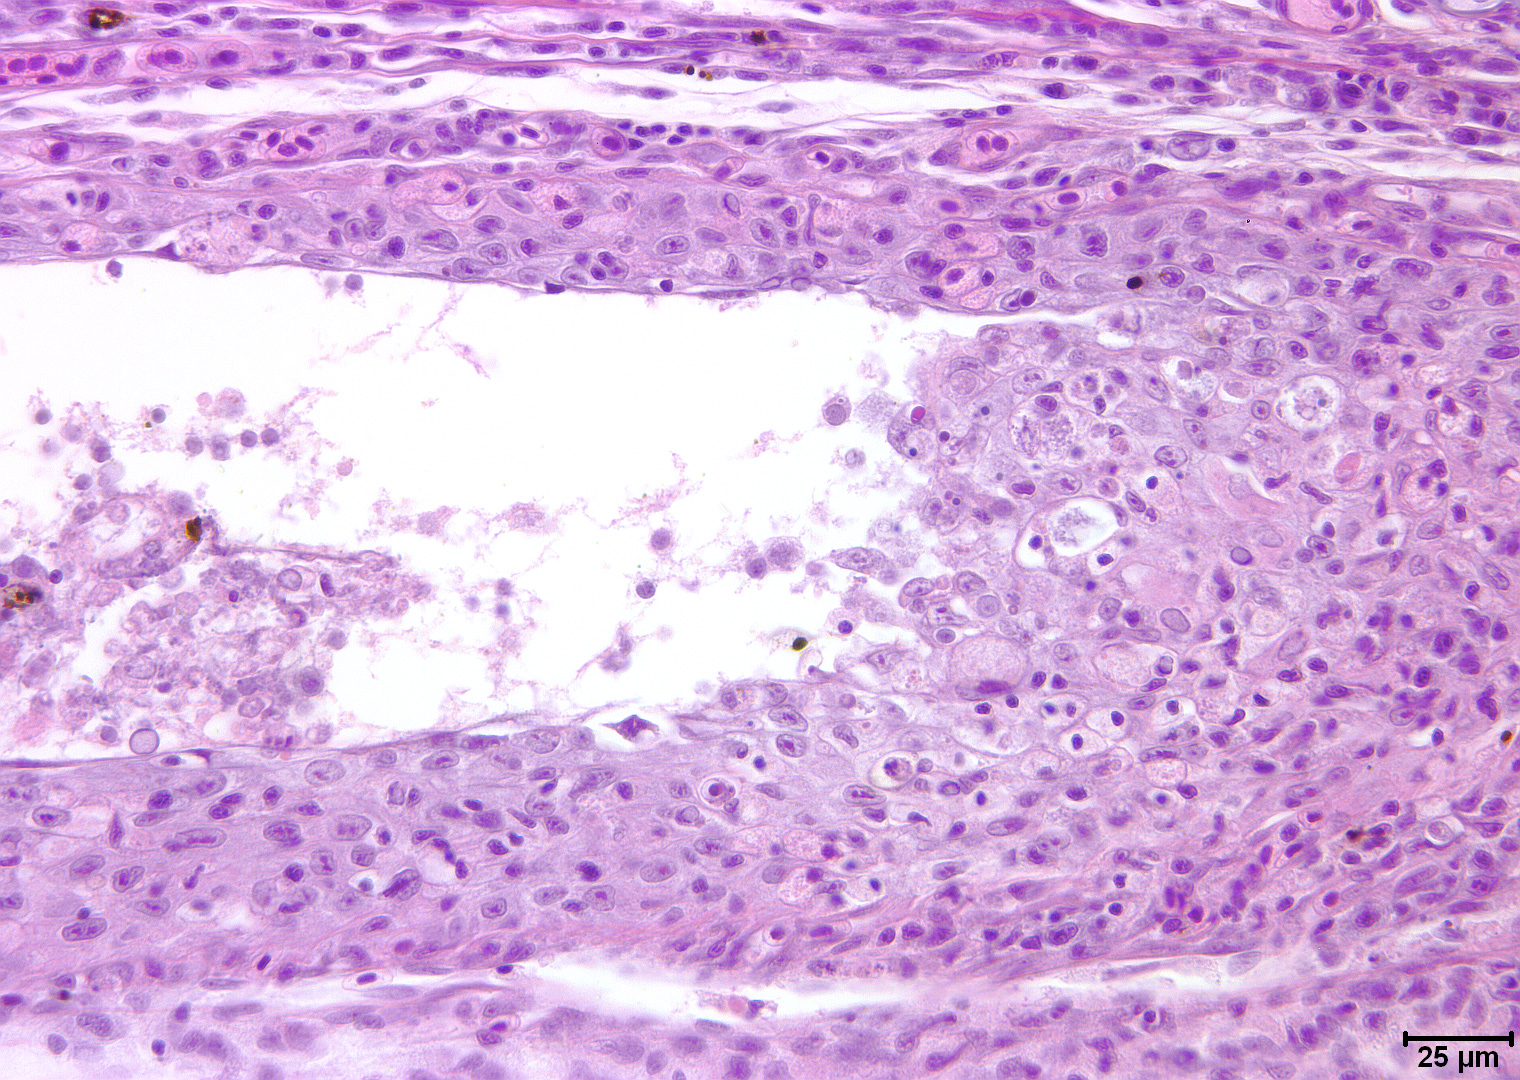

[症状]皮肤表面有许多石蜡状增生物,发病初期体表出现乳白色小斑点,随着病情发展,逐渐增大变厚,并蔓延全身,增生物略呈淡红或灰白色,可高出体表1〜2毫米。